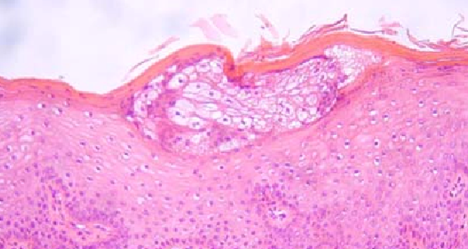

Mucinous cells with blue cytoplasm and flattened nuclei, intermixed with squamous cells containing dense eosinophilic cytoplasm and round nuclei. Courtesy Dr. V. Penopoulos.